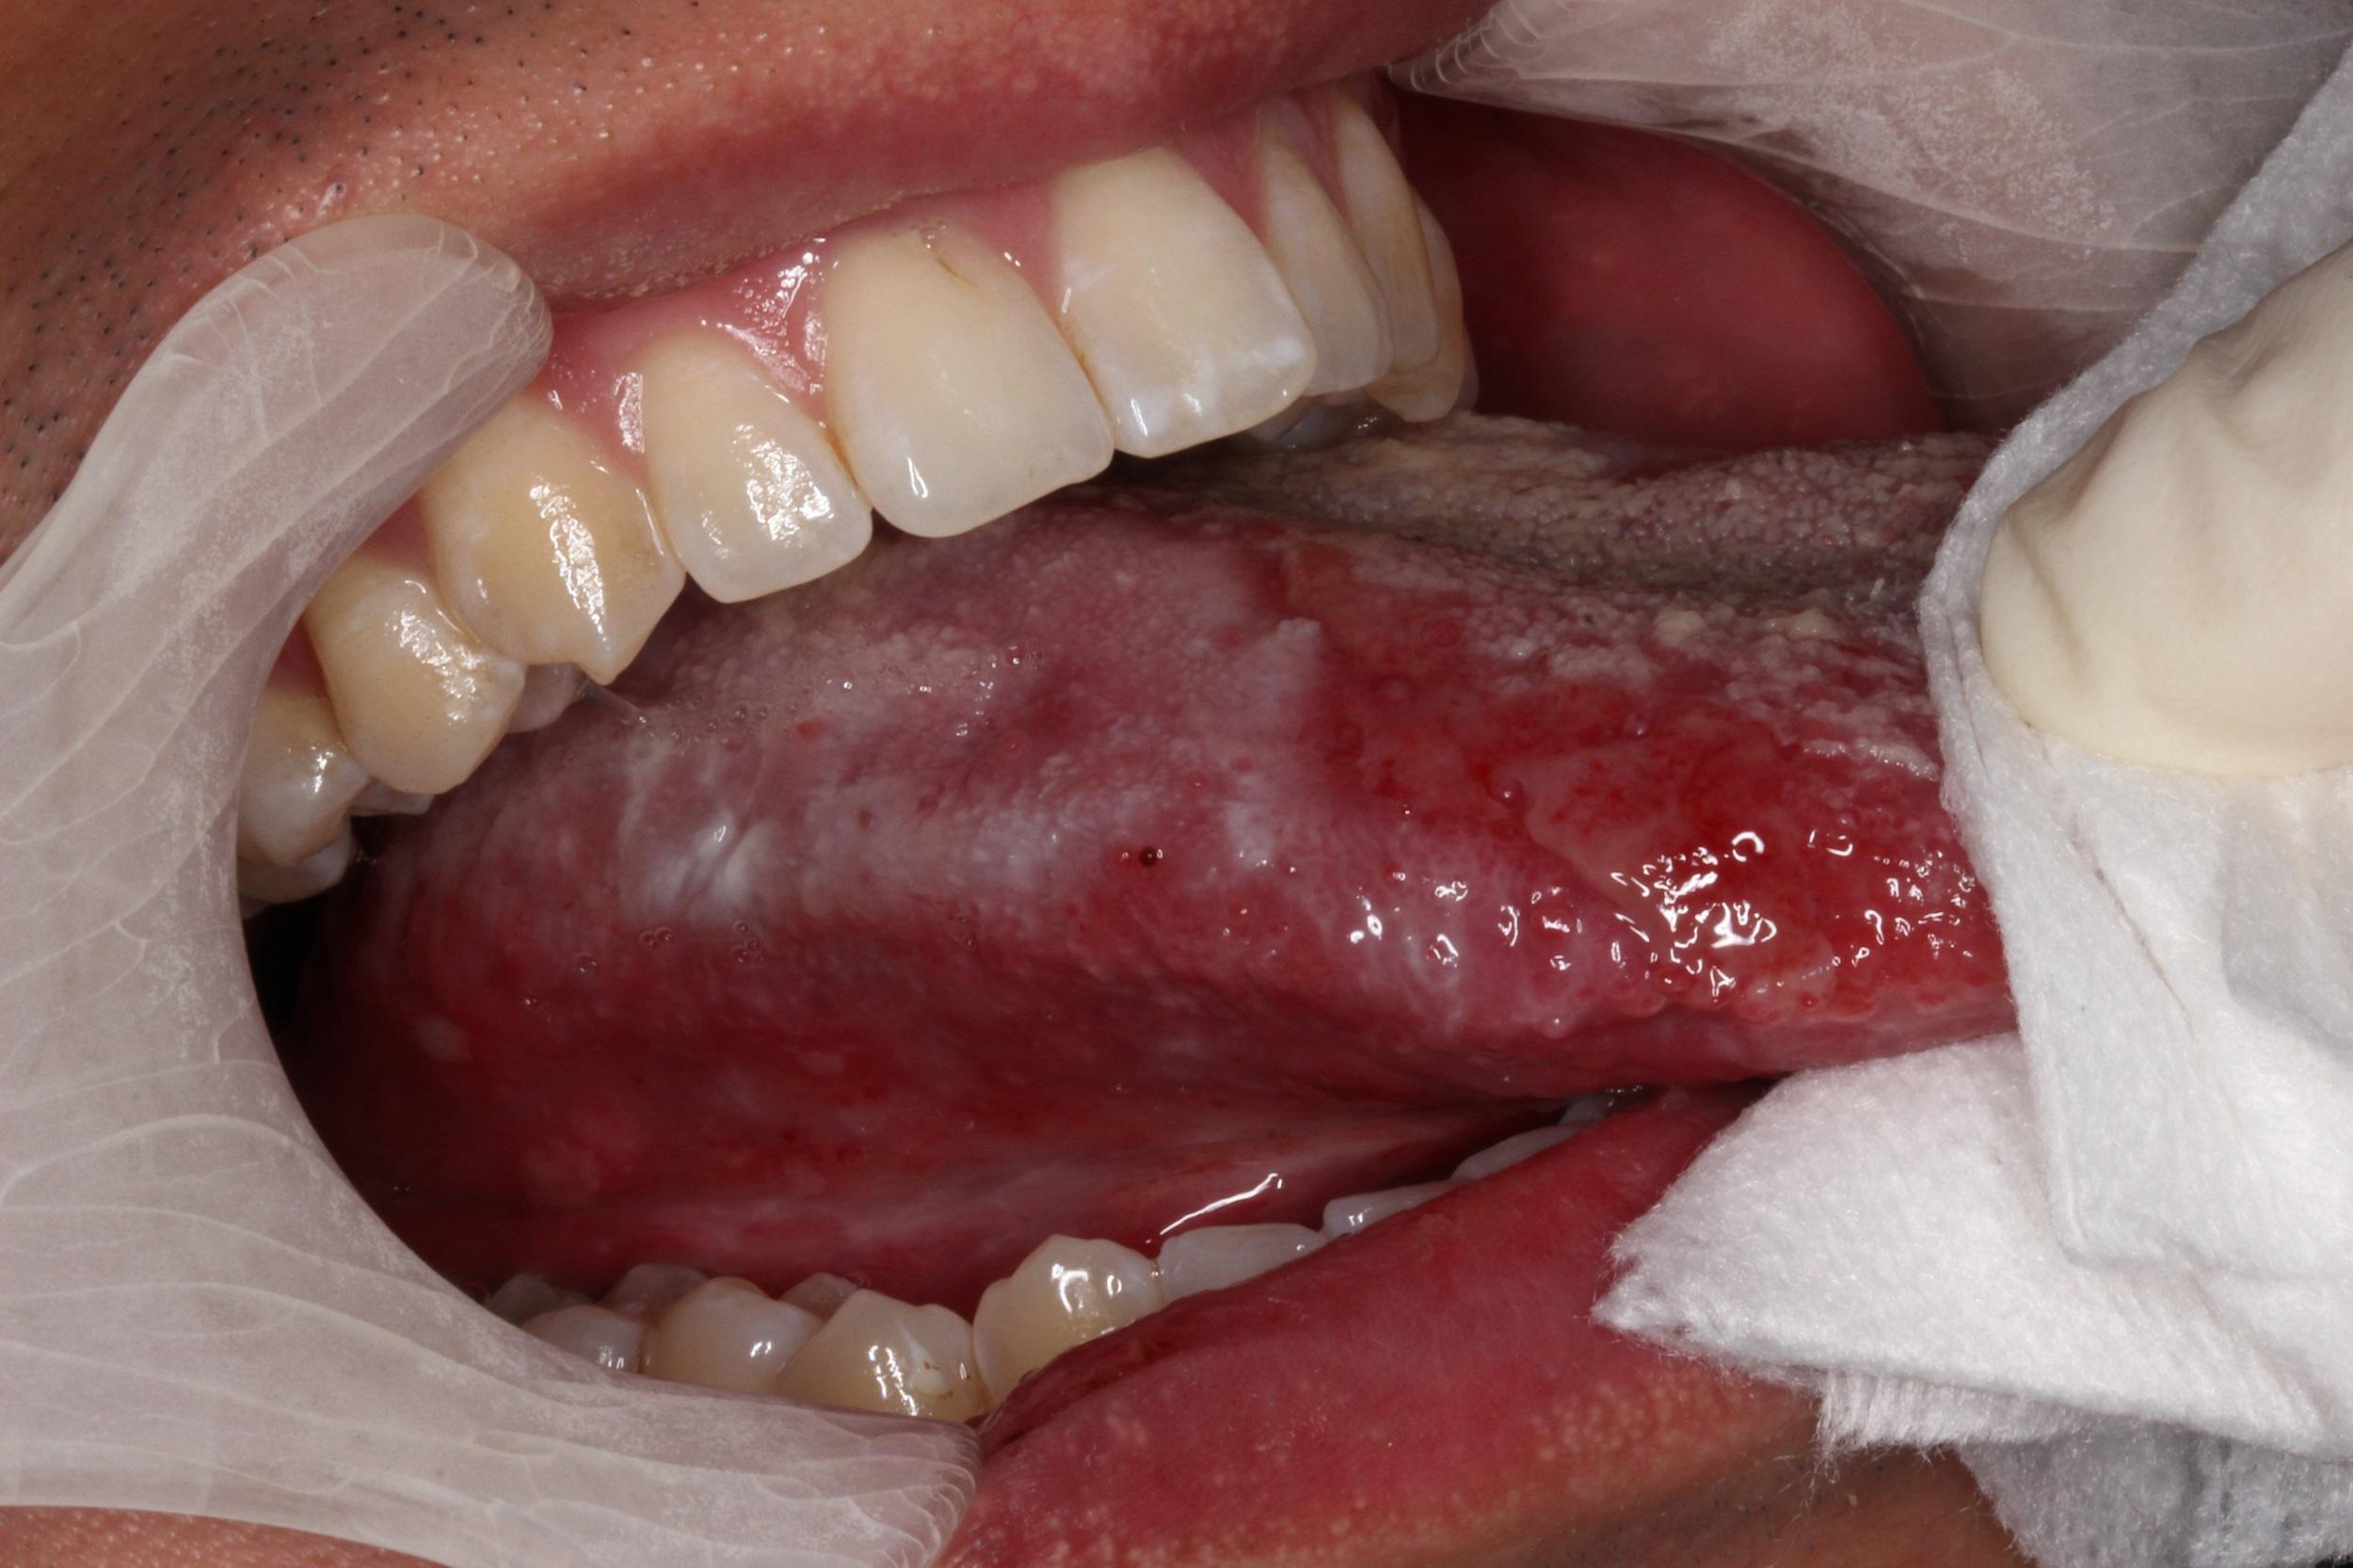

舌類扁平苔蘚黏膜炎

舌類扁平苔蘚黏膜炎或有癌變風險。